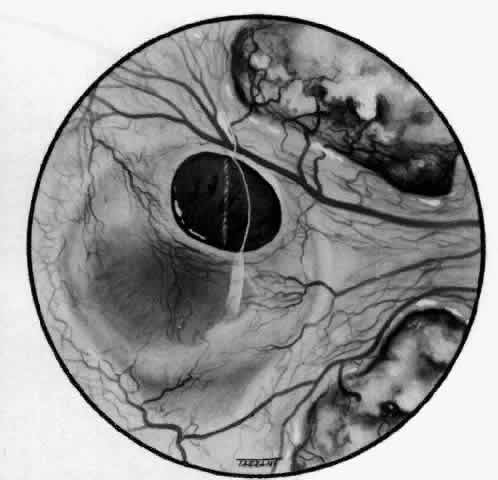

The sclera that is edematous is pushed forward, and the deep episcleral network is more congested than the superficial networks (Figs. 27 and 28). It is usually easy to ascertain by simple observation that the patient has scleritis and not episcleritis. However, it is not as easy to ascertain whether the patient has early necrotizing scleritis. It is in these patients that fluorescein angiography has considerable value, because the first changes are detectable in the ocular vasculature. Prompt and adequate treatment can prevent these changes from becoming irreversible.

Fig. 27. In scleritis, maximum congestion occurs in deep episcleral plexus, which is bowed forward by underlying scleral edema. Episcleral tissue is slightly infiltrated and superficial plexus is slightly congested (see Fig. 14). (Watson PG, Hayreh S, Awdry P: Episcleritis and scleritis. Br J Ophthalmol 52:278–279, 1968)

Fig. 28. Nodular scleritis. Both the anterior conjunctival slit and the deep scleral slit are displaced forward by the scleral edema. There is little separation between these two beams, indicating that all the edema is in the sclera and not in the overlying episclera. (Watson PG, Hayreh S, Awdry P: Episcleritis and scleritis. Br J Ophthalmol 52:278–279, 1968)